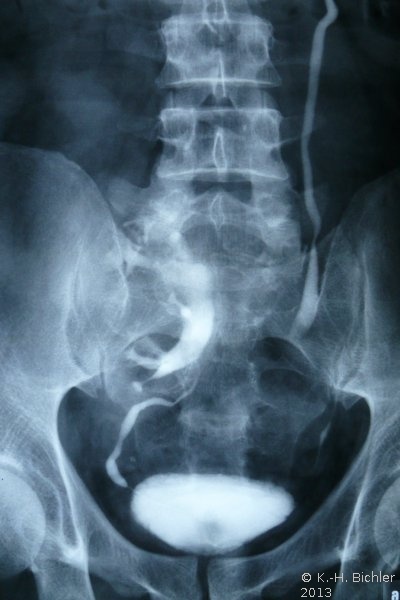

- Abbildung: Lumbale Dystopie

- Ausscheidungsurogramm: Glatte Abflussverhältnisse